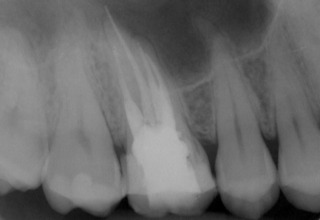

Nach Darstellung aller Wurzelkanaleingänge wird in einem zweiten Schritt das frakturierte Wurzelkanalinstrument dargestellt (Abb. 3 u. 4). Hierfür verwenden wir den Aufsatz 3E des Tigon+. Durch die schmale und lange Form des Instruments erreichen wir einen tiefen und schmalen Zugang.

Abb. 3 u. 4: Zustand nach Revision des Wurzelkanals und Darstellung des frakturierten Instruments.

Sofern es sich um ein kleines Frakturstück handelt, kann es durch aktive Übertragung von Energie des Ultraschalls zu einer Lockerung des Fragments kommen. Lockert es sich nicht, so „umkreist“ man das Instrument vorsichtig, um es anschließend mit einer Spritze gefüllt mit Palavit G zu greifen, zu fixieren und zu entfernen (Abb. 5). Nach Entfernung des Instruments erfolgt eine Kontrollaufnahme (Abb. 6).